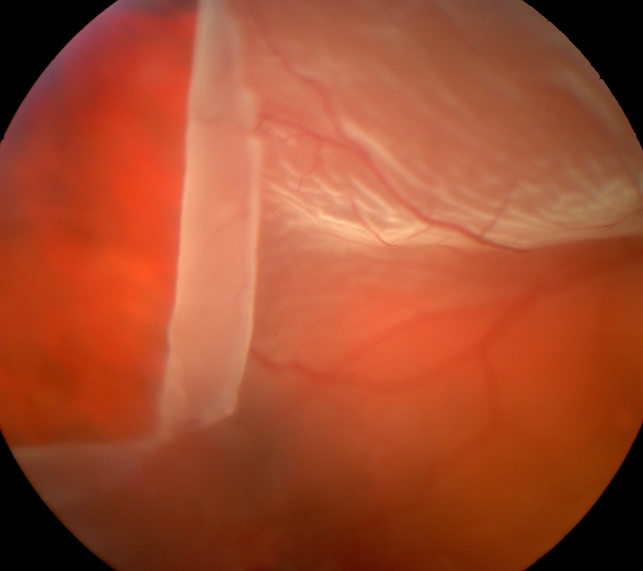

Complex Retinal Disorders

• giant retinal tear surgery